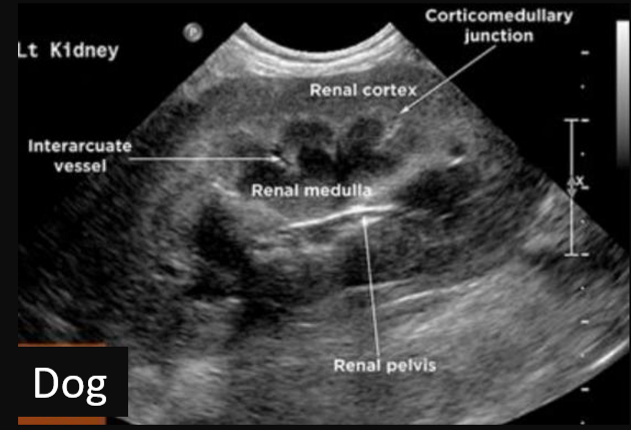

9

Q

Label this frontal/dorsal view kidney ultrasound

A